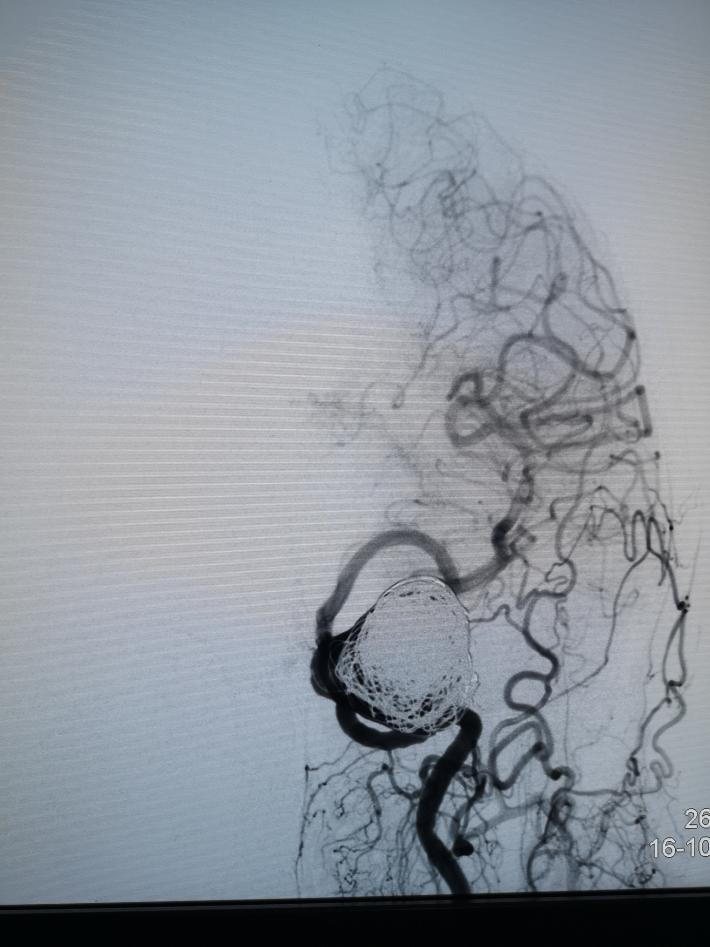

术中见海绵窦水平段巨大动脉瘤,瘤体造影剂明显滞留,且影响远端左侧远端血流。但前交通开放,对侧颈内动脉可完全代偿血流。

术中我们在密网支架导管无法到位的情况下,选择了常规的“支架辅助下动脉瘤介入栓塞术”,动脉瘤顺利得以治疗,由于瘤体巨大,且患者经济原因,无法做到致密填塞。

术后正侧位造影见,瘤体基本不显影,远端血流流速基本无延迟。